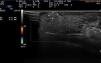

Physical examination showed a rounded well-defined nodule on the right side of the anterior third portion of the tongue. The yellowish nodule measured approximately 6mm at the longest axis, was reddish on the surface, flexible to the touch, and not adherent to deep layers. Dermatologic ultrasound with an 18MHz probe showed an oval tumor that was slightly more hypoechoic than the adjacent tissues. The well-defined but not encapsulated tumor measured 7.5×2.5mm on ultrasound and had no Doppler flow either on the surface or at the center. Fig. 1 shows the full length of the nodule. Suspecting a benign, avascular tumor, we performed a 4-mm punch biopsy. The histopathologic findings showed a proliferation of mature adipocytes distributed in small lobules separated by thin fibrous septa surrounded by normal stroma (Fig. 2). Our diagnosis based on these findings was lipoma of the tongue.

After the biopsy, 2.5mm of the lesion remained (Fig. 3). As the lesion was benign and asymptomatic, we were guided by the patient's preference and chose to wait and watch for changes.